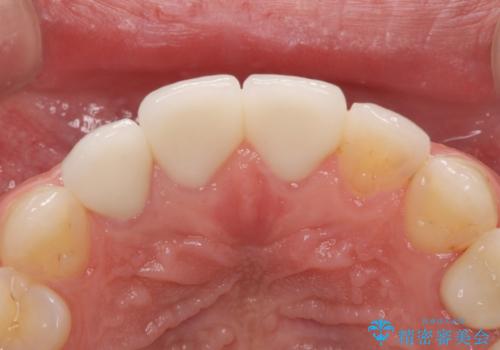

適合が良い被せ物が入りました。

隙間がなく被せ物が入ることによりう蝕の再発のリスクが低くなります。